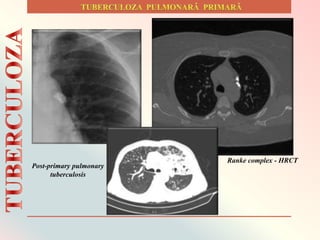

Şancrul de inoculare

sau afectul primar unic sau

multiplu, datorită

dimensiunilor foarte mici

este greu de evidenţiat.

Adenopatia satelită de

dimensiuni variabile, de

obicei unilaterală se

caracterizează prin

afectarea frecventă a

ganglionilor hilari şi

paratraheali.

Ranke complex - HRCT

Post-primary pulmonary

tuberculosis

Infecţia se propagă pe cale limfatică spre ganglionii sateliţi regionali,

determinând apariţia adenopatiei localizate hilar sau paratraheal.